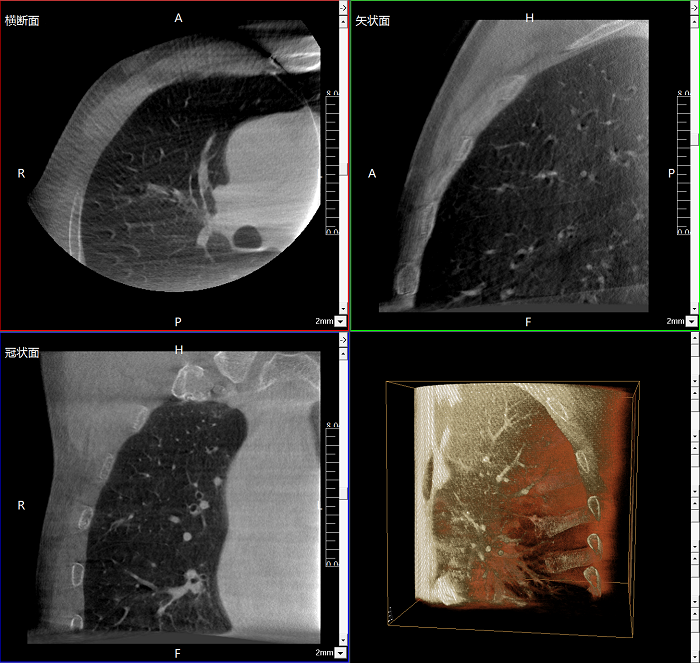

三維成像 全面觀察

任意視角、任意切面觀察

術中實時生成橫斷面、矢狀面、冠狀面及三維影像,可在任意切面、任意角度評估植入物和解剖結構的相對位置。

術中CT檢查 減少翻修概率

通過術中三維影像的檢查,可以立即發(fā)現(xiàn)植入物的錯位,減少不必要的第二次手術,減少并發(fā)癥概率以及感染風險。

Clinical picture

臨床圖片